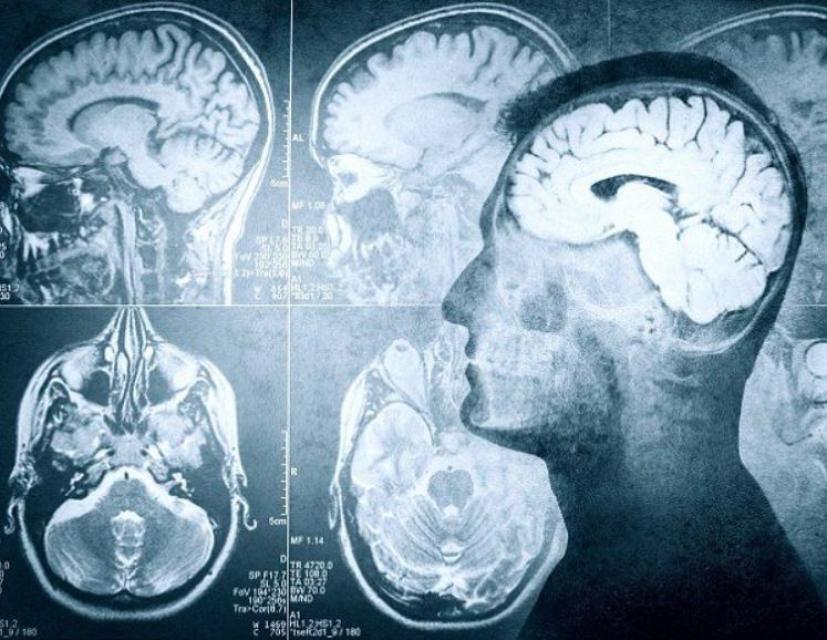

Πολλές δοξασίες, περισσότερες εικασίες και ακόμη περισσότερες σκέψεις… Τι συμβαίνει άραγε στον ανθρώπινο εγκέφαλο λίγο πριν επέλθει ο θάνατος;

Στο παραπάνω ερώτημα επιχειρούν να δώσουν απάντηση οι επιστήμονες, συγκεντρώνοντας στοιχεία από μεγάλη έρευνα που διεξήγαγαν τα τελευταία χρόνια.

Τα αποτελέσματα από την έρευνα μίας ομάδας νευρολόγων από το Charité–Universitätsmedizin στο Βερολίνο, ήταν ομολογουμένως εκπληκτικά. Οι ερευνητές χρησιμοποίησαν ηλεκτρόδια ώστε να «διαβάσουν» τις αντιδράσεις του ανθρώπινου εγκεφάλου, λίγο πριν επέλθει το τέλος.

Αυτό που διαπιστώθηκε, είναι ότι ακόμη και πέντε λεπτά μετά τη διακοπή λειτουργίας της καρδιάς, τα εγκεφαλικά κύτταρα παραμένουν ζωντανά και εξακολουθούν να λειτουργούν. Η δε συνείδηση του ατόμου, παραμένει «ζωντανή» για ακόμη μεγαλύτερο διάστημα, παρ’ ότι όντως το σώμα έχει πεθάνει και δεν μπορεί να επανέλθει.

Το πιο εντυπωσιακό στοιχείο, ωστόσο, είναι το εξής: Το τελευταίο λεπτό πριν «κλείσει» ο εγκέφαλος, εμφανίζεται ένα «τσουνάμι» αντιδράσεων, τις οποίες οι επιστήμονες χαρακτήρισαν «εξάπλωση της κατάθλιψης».

Με άλλα λόγια, όταν τα εγκεφαλικά κύτταρα συνειδητοποιούν ότι το σώμα έχει πεθάνει, καταρρέουν και αντιδρούν όπως αντιδρούν κατά την περίοδο που ο άνθρωπος έχει περιέλθει σε καταθλιπτικό σοκ.